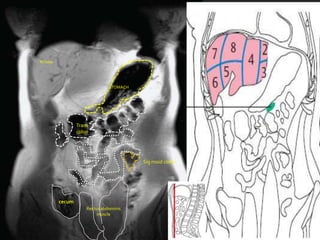

STOMACH

PANCREAS

Trns col

Trans

colon

Sig moid colon

cecum

Rectus abdominis

muscle